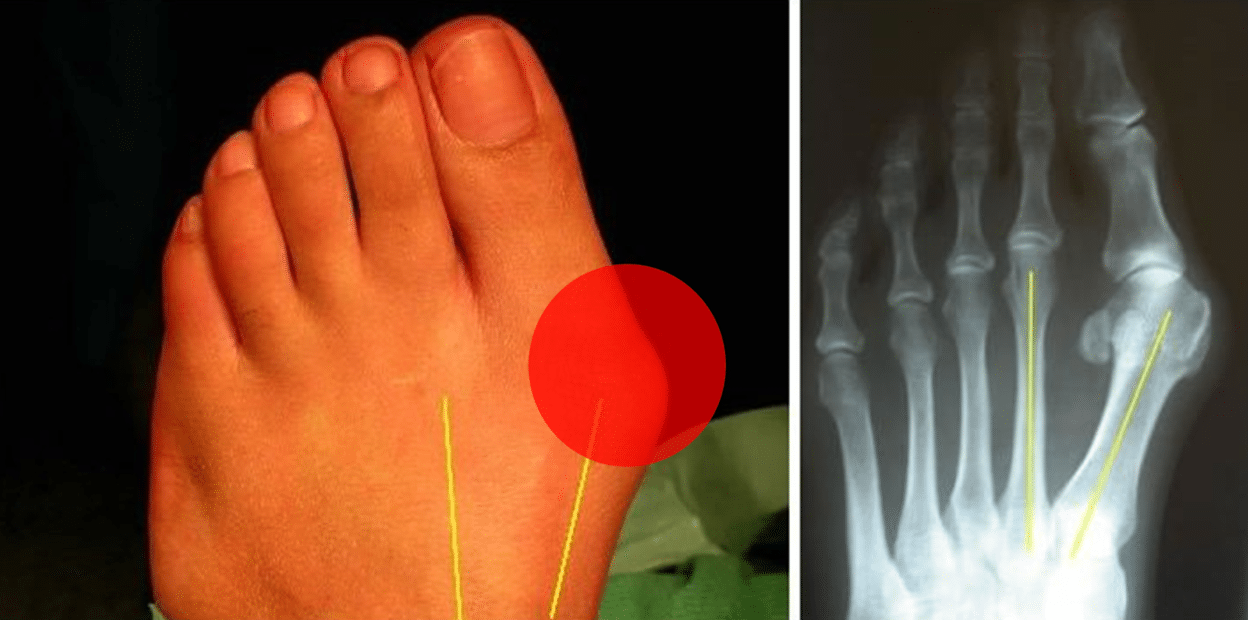

重度拇外翻

拇外翻手术图解

拇外翻的矫治

拇外翻